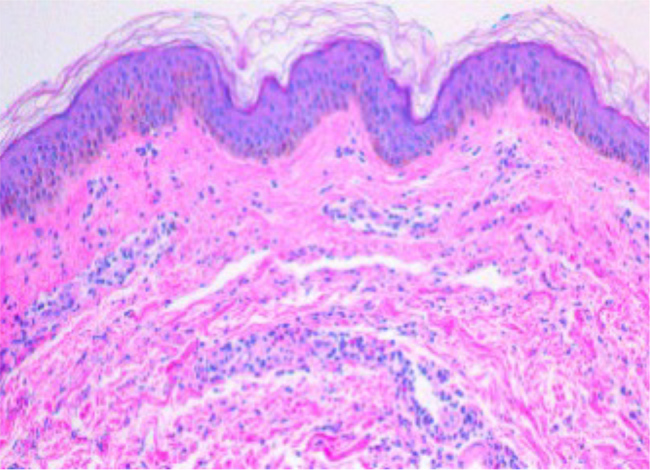

原发性血小板增多症(ET)是一种慢性骨髓增生性肿瘤,其特征是持续的血小板增多,通常与JAK2 V617F突变有关。它主要以其血栓和出血性并发症而闻名,这是其主要的临床表现。然而,炎症和皮肤病的表现是不常见的,不太为人所知。其中,皮肤血管炎,尤其是白细胞破坏性血管炎(LCV)是一种罕见且未被报道的特征。我们提出的病例54岁的妇女与jak2阳性ET谁发展持续性荨麻疹,同时恶化的血小板增多。骨髓活检显示巨核细胞增生,证实ET的诊断。最初,患者对羟基脲有反应,但她的疾病最终变得难治性,阿纳格列德未能控制她的血小板计数或症状。她的皮疹进展与不受控制的血小板增多同时发生,活检证实LCV。开始使用ruxolitinib(一种JAK1/2抑制剂)导致血液学改善和血管炎的完全解决。该病例强调了ET与皮肤血管炎之间罕见但具有临床意义的关联,并提示JAK抑制在治疗此类难治性炎症表现中的潜在作用。学习要点:皮肤血管炎是原发性血小板增多症的一种罕见但重要的表现。白细胞分裂性血管炎可能伴有对标准治疗有抗性的荨麻疹病变。ruxolitinib抑制Janus激酶(JAK)可以在难治性病例中实现血液和皮肤缓解。

Essential thrombocythemia (ET) is a chronic myeloproliferative neoplasm characterised by sustained thrombocytosis and frequently associated with JAK2 V617F mutations. It is primarily known for its thrombotic and haemorrhagic complications, which dominate its clinical presentation. However, inflammatory and dermatologic manifestations are uncommon and less well recognised. Among these, cutaneous vasculitis - particularly leukocytoclastic vasculitis (LCV) - is a rare and underreported feature. We present the case of a 54-year-old woman with JAK2-positive ET who developed a persistent urticarial rash that coincided with worsening thrombocytosis. Bone marrow biopsy revealed megakaryocytic hyperplasia, confirming the diagnosis of ET. Initially, the patient responded to hydroxyurea, but her disease eventually became refractory, and anagrelide failed to control either her platelet count or symptoms. Her skin rash progressed in parallel with uncontrolled thrombocytosis, and biopsy confirmed LCV. Initiation of ruxolitinib, a JAK1/2 inhibitor, led to haematologic improvement and complete resolution of the vasculitis. This case highlights a rare but clinically significant association between ET and cutaneous vasculitis and suggests a potential role for JAK inhibition in managing such refractory inflammatory manifestations.

Learning points: Cutaneous vasculitis is a rare but significant manifestation of essential thrombocythemia.Leukocytoclastic vasculitis may present with urticarial lesions resistant to standard therapy.Janus kinase (JAK) inhibition with ruxolitinib can achieve both haematologic and dermatologic remission in refractory cases.